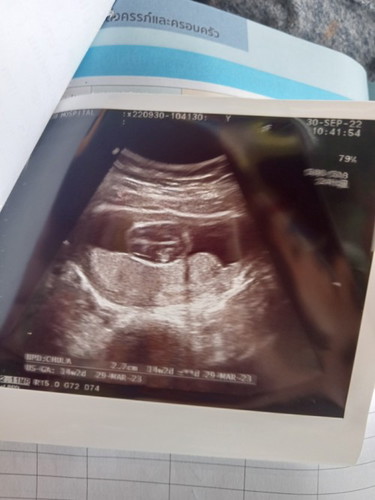

ไปซาวด์มา14/2ค่ะดูไม่เป็นไม่รู้ว่าตัวเป็นอยู่ใน14/2 ยังเป็นก้อนเลือดหรือเป็นตัวแล้วค่ะ

เป็นตัวแล้วค่า ในรูปเป็นศีรษะน้อง กับรกค่ะ